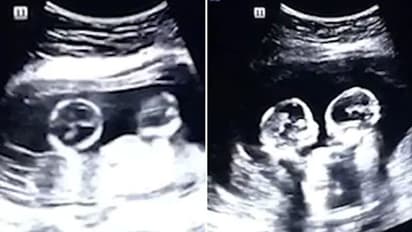

ಬೀಜಿಂಗ್[ಏ.17]: ತಾಯಿ ಹೊಟ್ಟೆಯಲ್ಲಿದ್ದ ಅವಳಿ ಮಕ್ಕಳು ಹೊಡೆದಾಡಿಕೊಂಡು ಜಗಳೋವಾಡುತ್ತಿರುವ ವಿಡಿಯೋ ಒಂದು ಸಾಮಾಜಿಕ ಜಾಲತಾಣಗಳಲ್ಲಿ ವೈರಲ್ ಆಗುತ್ತಿದೆ. ಅಧಿಕ ಸಂಖ್ಯೆಯಲ್ಲಿ ಈ ಅಲ್ಟ್ರಾಸೌಂಡ್ ವಿಡಿಯೋ ವೀಕ್ಷಿಸಲಾಗುತ್ತಿದ್ದು, ಪ್ರೇಕ್ಷಕರು ಇದನ್ನು ಬಹಳಷ್ಟು ಇಷ್ಟ ಪಡುತ್ತಿದ್ದಾರೆ.

ಇದು ಚೀನಾದಲ್ಲಿ ನಡೆದ ಘಟನೆಯ ವಿಡಿಯೋ ಎನ್ನಲಾಗಿದೆ. 2018ರಲ್ಲೇ ಇದು ಚೀನಾದಲ್ಲಿ ಶೇರ್ ಮಾಡಲಾಗಿತ್ತು ಎಂದು ಮಾಧ್ಯಮಗಳು ವರದಿ ಮಾಡಿವೆ. ನಾಲ್ಕು ತಿಂಗಳ ಗರ್ಭಿಣಿ ಮಹಿಳೆಯ ಅಲ್ಟ್ರಾಸೌಂಡ್ ವಿಡಿಯೋ ಇದಾಗಿದೆ. ಪರೀಕ್ಷೆಗೆಂದು ಆಸ್ಪತ್ರೆಗೆ ತೆರಳಿದ್ದ ವೇಳೆ ಅವಳಿ ಮಕ್ಕಳು ಪರಸ್ಪರ ಮುಖಕ್ಕೆ ಹೊಡೆದು ಜಗಳವಾಡುತ್ತಿರುವುದು ಗಮನಕ್ಕೆ ಬಂದಿದೆ. ಆ ಕೂಡಲೇ ಮಕ್ಕಳ ತಂದೆ ಟಾವೋ ಈ ವಿಡಿಯೋ ಚಿತ್ರೀಕರಿಸಿದ್ದಾರೆ.

ಚೀನಾದ ಸ್ಥಳೀಯ ಮಾಧ್ಯಮಗಳಿಗೆ ಪ್ರತಿಕ್ರಿಯೆ ನೀಡಿರುವ ಮಕ್ಕಳ ತಂದೆ 'ಹೊಟ್ಟೆಯೊಳಗಿದ್ದ ಮಕ್ಕಳು ಬಹಳಷ್ಟು ಸಮಯ ಪರಸ್ಪರ ಹೊಡೆದಾಡಿಕೊಂಡಿದ್ದವು' ಎಂದಿದ್ದಾರೆ. ಈ ವಿಡಿಯೋ 2 ಮಿಲಿಯನ್ ಗೂ ಅಧಿಕ ಮಂದಿಯಿಂದ ವೀಕ್ಷಿಸಲ್ಪಟ್ಟಿದೆ.

ಈಗ ಮಕ್ಕಳು ಜನಿಸಿದ್ದು, ಚೆರಿ ಹಾಗೂ ಸ್ಟ್ರಾಬೆರಿ ಎಂದು ನಾಮಕರಣ ಮಾಡಿದ್ದಾರೆ. ಹೀಗಿದ್ದರೂ ಈ ವಿಡಿಯೋ ಇವತ್ತಿಗೂ ಸೋಶಿಯಲ್ ಮೀಡಿಯಾದಲ್ಲಿ ಬಹಳಷ್ಟು ಹರಿದಾಡುತ್ತಿದೆ. 'ಹೊಟ್ಟೆಯೊಳಗೇ ಹೀಗೆ ಜಗಳವಾಡಿದ್ದಾರೆ ಆದರೆ ಹೊರ ಬಂದ ಬಳಿಕ ಪರಸ್ಪರ ಪ್ರೀತಿಯಿಂದ ಇರುತ್ತಾರೆ' ಎಂದು ವೀಕ್ಷಕನೊಬ್ಬ ಕಮೆಂಟ್ ಮಾಡಿದ್ದಾನೆ.